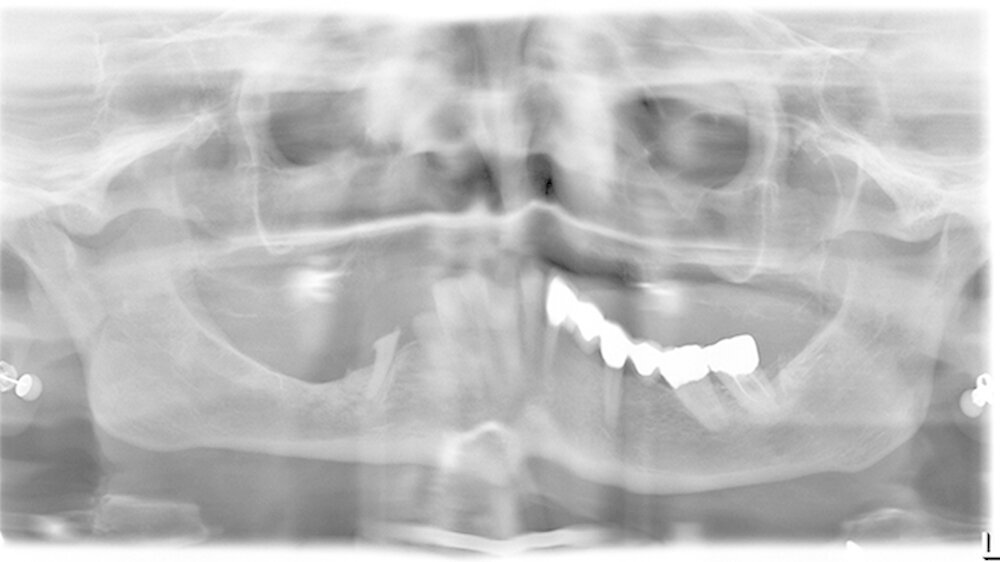

Die Patientin war multimorbide und deshalb zuvor mehrere Wochen stationär behandelt worden. Sie war in einem sehr schlechten Allgemeinzustand, immobil und wurde im Rollstuhl gebracht. Eine Röntgenuntersuchung zeigte keinen Befund, außer einer Überportion Haftcreme unter der Oberkieferprothese. Die Patientin wurde angehalten, diesen Überschuss daheim zu entfernen. Bei ihrem zweiten Besuch kam sie ohne Prothese und die Zahnärztin konnte den Gaumen genauer inspizieren.